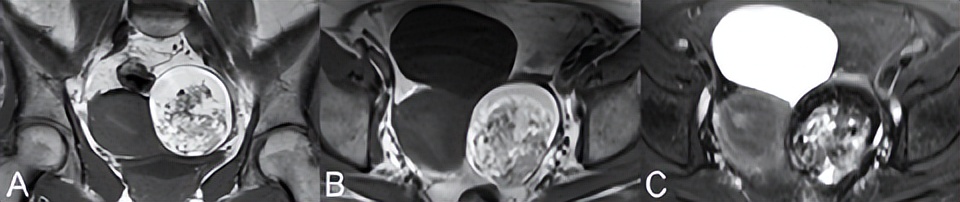

功能性滤泡性卵巢囊肿是常见的良性病变,通常表现为单房、薄壁病变,伴有水样信号(图76.1,轴位T2WI)。无功能性囊性病变是鉴别诊断因素,但由于肿瘤形成可能看起来相似,因此应在6周内通过超声重新评估新诊断的30 mm以上卵泡囊肿。滤泡囊肿的囊壁增强不如黄体囊肿。后者的壁通常也较厚,如图76.2A的冠状T2WI(白色箭头)所示,(B) CE T1WI显示管壁明显增强。

出血性黄体囊肿很常见,在图76.2C中示出,在轴位(C,白色箭头)T1和(D) T2WI上D分别为高信号和低信号。多囊卵巢综合征(PCOS)和卵巢过度刺激综合征中可见多个双侧囊肿。在多囊卵巢综合征中,根据定义,此类囊肿小于10 mm,位于外周和包膜下,与突出的低信号中心间质相邻。在卵巢过度刺激综合征中,囊肿可能较大且为非外周性囊肿。对于后者,可能出现腹水和胸腔积液,同时扭转风险增加。

畸胎瘤可能含有囊性成分。皮样囊肿(即成熟囊性畸胎瘤)通常含有分泌脂肪皮脂腺物质的突出外胚层。通常会出现含有脂肪、毛发、骨骼或牙齿的实心非增强性突起(即Rokitansky)。图76.3中的(A)冠状位和(B)轴位T1WI显示了一个不均匀出现的囊性肿块,具有明显的高信号成分。这种高信号可见于出血性囊肿和子宫内膜异位,但(C)脂肪抑制T2WI上的信号丢失证实了皮样囊肿的存在。STIR抑制脂肪是非特异性的(即所有T1短的质子都被抑制),不能进行上述区分。微小脂肪含量可能无法通过频率饱和检测到

▲ 图76.2

可通过同反相位GRE T1WI上的信号减低更好地识别。增强,实性成分有利于恶性肿瘤诊断,比如未成熟的畸胎瘤。皮样囊肿易导致卵巢扭转,最初表现为基质水肿样信号,但由于坏死和出血,信号随时间变化。CE T1WI无增强是卵巢梗死的特异性表现,但考虑到卵巢的双重血供,对扭转不敏感。其他发现包括同侧子宫偏斜、腹水和卵巢血管充血。